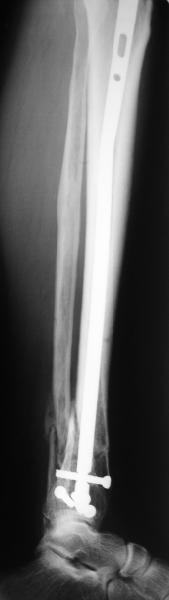

Very interesting application, but is the final position in a little distal varus with some fibula

distraction? Would that have been eliminated by fibula plating?

At least both the ankle mortise and tibial alignment look acceptable, don't they?

I am just trying to illustrate that prevention of 1)tibial valgus and 2)loss of reduction can be provided without fibular plating. Small changes of conventional nailing techniques allow to maintain reduction of the tibia reliably without adjunctive fibular stabilization.

In delayed cases acute length restoration performed only in the tibia may leave the fibula shortened thus change the mortise. So it is reasonable to restore length of both bones simultaneously by distractor and fix the fibula not with open reduction and plating but just by a single perQ screw. Example attached.